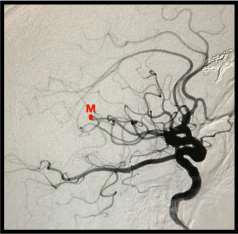

De acordo com o ponto M representado na angiografia abaixo, assinale a alternativa CORRETA.

Fonte da Imagem: cedida pelo autor